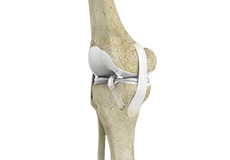

Patellofemoral Knee Replacement

The knee can be divided into three compartments: patellofemoral, the compartment in front of the knee between the kneecap and thighbone, the medial compartment, on the inside portion of the knee, and lateral compartment which is the area on the outside portion of the knee joint.

Arthritis of the knee can cause pain and stiffness, making regular activities such as walking and bending difficult. As arthritis progresses, conservative treatments tend to lose their efficacy and more definitive treatment should be considered. Knee replacement surgery involves replacing worn or damaged joints with implants to reduce pain and improve movement.